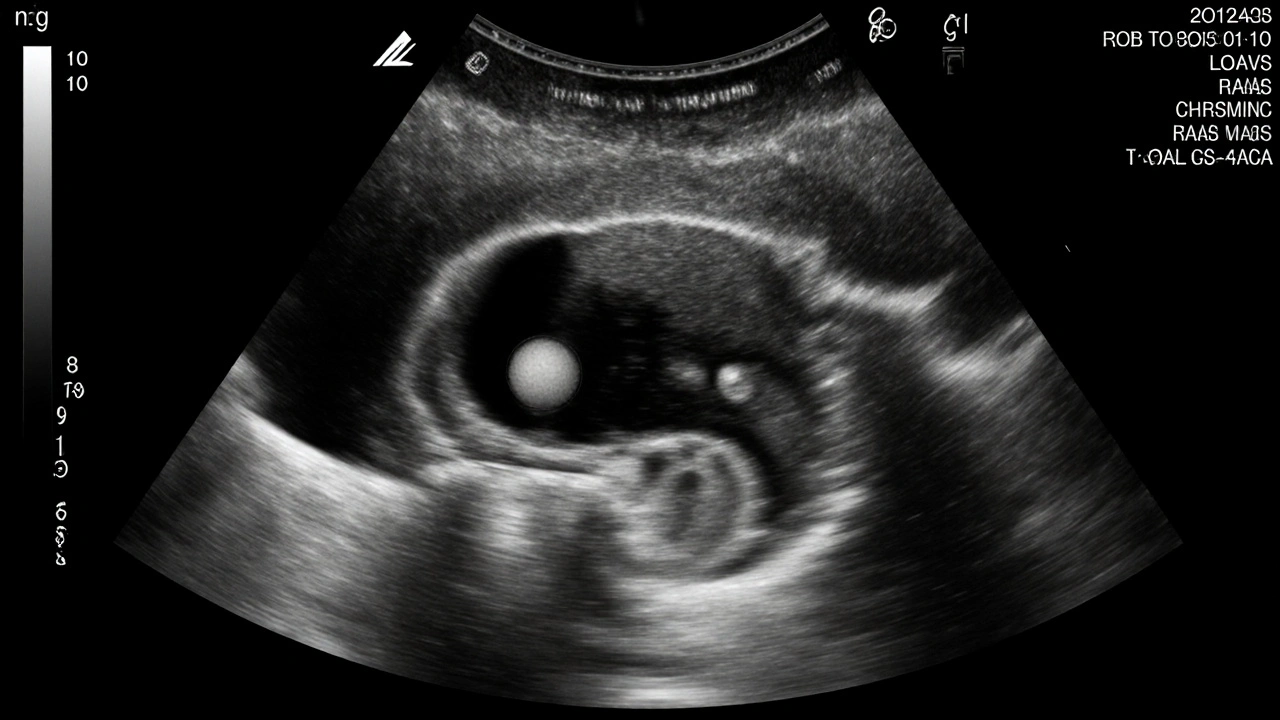

V 5 týdnu těhotenství je plod ještě jen malým zárodkem o velikosti hrášku - asi 2-5 milimetrů. Na transvaginálním ultrazvuku, který je v tomto období nejčastěji používaný, můžete vidět:

• Plodový váček (gestační váček) - první jasná známka těhotenství. Je to malá, tmavá kruhová struktura v děloze, která obsahuje plod a později i plodovou vodu.

• Žloutkový váček - malý, kulatý útvar vedle plodového váčku. Jeho úloha je výživa plodu v raném stádiu, než se vyvinou placentální cévy. Jeho viditelnost je dobrým znamením, že těhotenství probíhá normálně.

• Embryonální pohyb - v některých případech, pokud je ultrazvuk kvalitní a těhotenství pokročilé, můžete spatřit i první pulzace srdce. To se obvykle objevuje kolem 5. a 6. týdne.

Ne vždy však všechny tyto prvky najednou vidíte. Pokud je termín těhotenství přesně stanoven podle poslední menstruace a ultrazvuk je proveden transvaginálně, je pravděpodobnost viditelnosti srdce kolem 70-80 %. Pokud jste však o týden dříve, může být srdce ještě příliš malé, aby bylo detekovatelné.